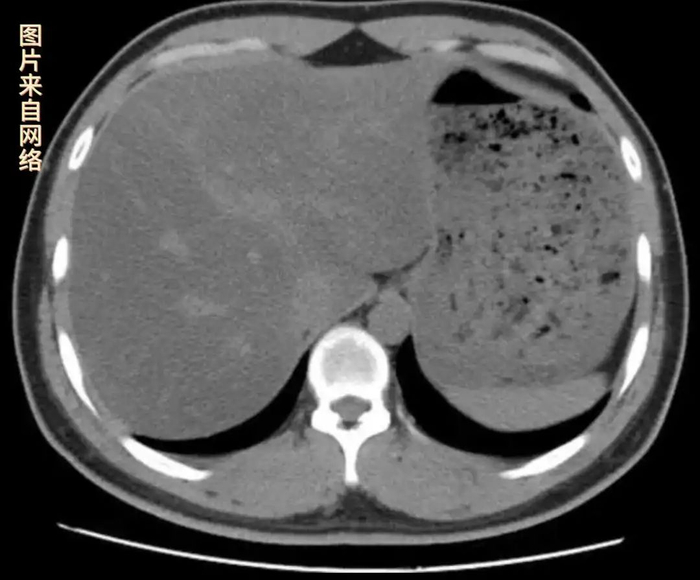

刘女士说,半年前她在体检中查出轻度脂肪肝,于是戒掉了荤腥和碳水,每餐基本是水煮叶子菜加上蒸杂粮。经过半年时间,刘女士的体重减掉了10斤左右,B超一查,脂肪肝反而成了中重度。这是怎么回事呢?

医生提醒,不健康不科学减肥,尤其是过度节食,蛋白质摄入严重不足,反而可能会加重脂肪肝。肝脏是人体负责代谢和排毒的器官,在肝组织中有3%到5%的脂肪,超过这个范围,就属于脂肪肝。如果任由脂肪肝发展,可能会出现肝脏增大甚至肝硬化的症状。远离脂肪肝一定要有良好的生活习惯。